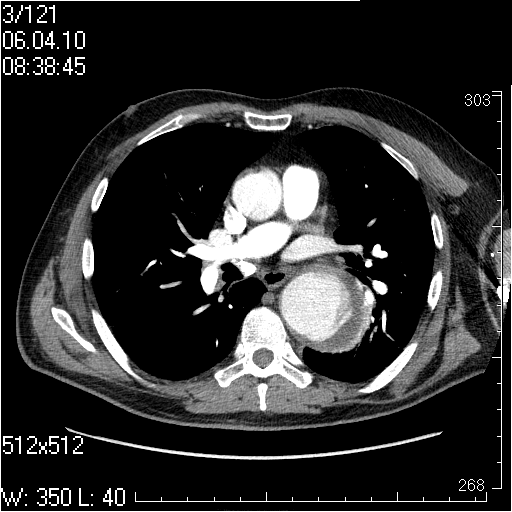

Грудной отдел аорты

Пожилой мужчина, жалоб в настоящее время не предъявляет.